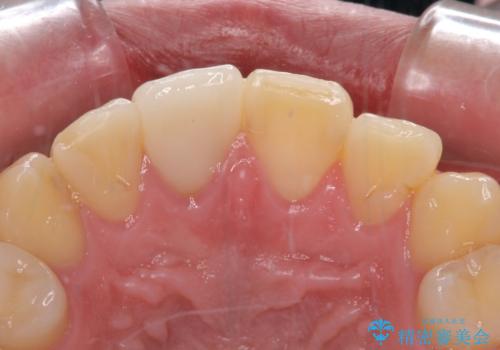

- 治療中の前歯と口腔内にある銀歯が気になるとのことで来院された患者様です。

土台に含まれている金属も含め、口腔内の金属は全て除去し、根管治療が必要な歯は根管治療を行い、オールセラミッククラウンやセラミックインレーにて治療することとしました。

途中来院されない時期があったため、初診から終了まで期間がかかりましたが、根管治療を行った歯の根尖病変はいずれも改善を確認することができました。

口腔内の金属が全てなくなり、患者様には大変満足していただきました。